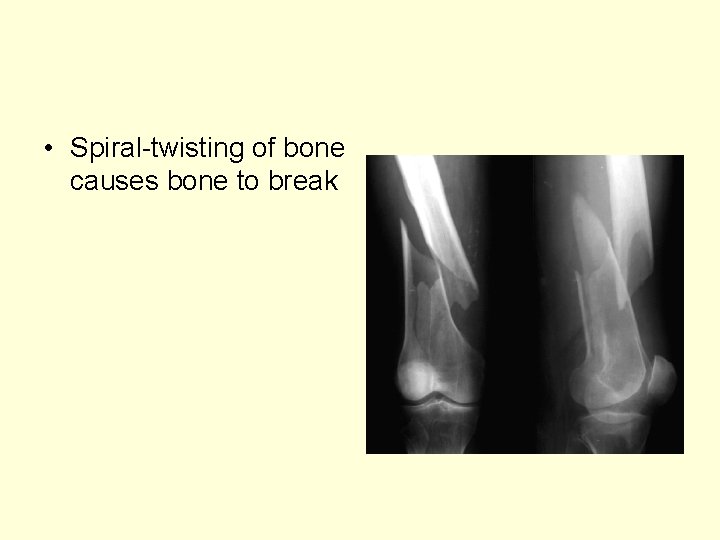

• Spiral-twisting of bone causes bone to break